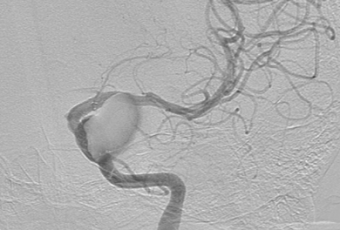

2 этап. По методике Сельдингера в левую ОСА установлен радиальный интродьюсер 6F. При помощи гидрофильного проводника Radifocus интракраниально введен направляющий катетер Fargo 6F. Затем при помощи микропроводника Traxcess14 область поражения – фузиформная аневризма кавернозного сегмента преодолена. Проводник заведен в левую СМА до уровня М3. Потом осуществлена замена микрокатетера на манипуляционный катетер Headway 27, кончик которого позиционирован в М1-сегменте левой СМА. Далее введено устройство, отклоняющее поток (FRED 4*32*26 мм). Стент позиционирован и имплантирован из-под бифуркации ВСА с перекрытием области поражения (3-х аневризм ВСА). Стент раскрыт полностью. При контрольной ангиографии левая ВСА проходима, стент прилежит к стенкам артерии; отмечается длительная стагнация контрастного вещества в гигантской аневризме; церебральные ветви проходимы, бессосудистых зон нет.

Неврологический статус пациентки без отрицательной динамики, отмечен частичный регресс глазодвигательных нарушений.

Окончательный исход операции (степень окклюзии аневризм) будет оценен через 6 месяцев после завершения дезагрегантной терапии.